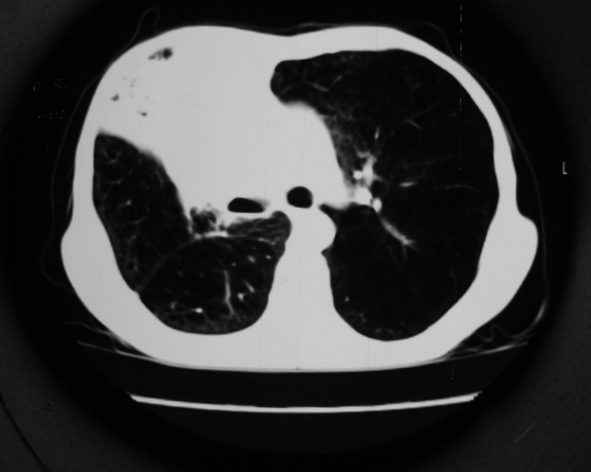

男53岁,咳嗽气短,以往身体健康.

右肺上叶多发多形态空洞及增殖灶,可见团块钙化,胸膜肥厚、粘连,考虑继发型肺结核可能性大

1.右肺上叶干酪性肺炎,2。肺气肿,肺大泡

右肺上中叶结核干酪性肺炎

右肺中上叶干酪性肺炎。

支持右上肺继发性肺结核并干酪性肺炎,右肺大泡,左肺代偿性气肿。